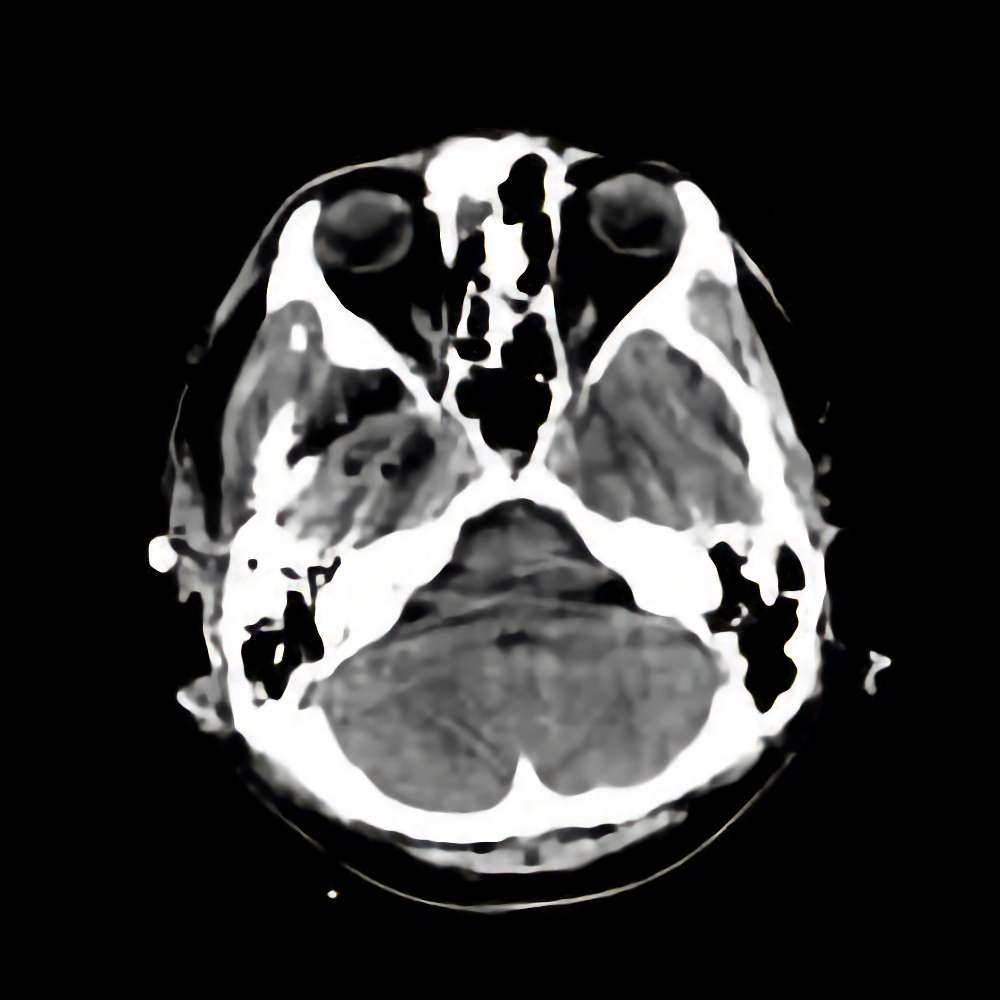

症例 '16年6月

No.

’16_96

'16年6月

40代

髄膜腫

断層撮影

手術前

1

手術前2

手術後